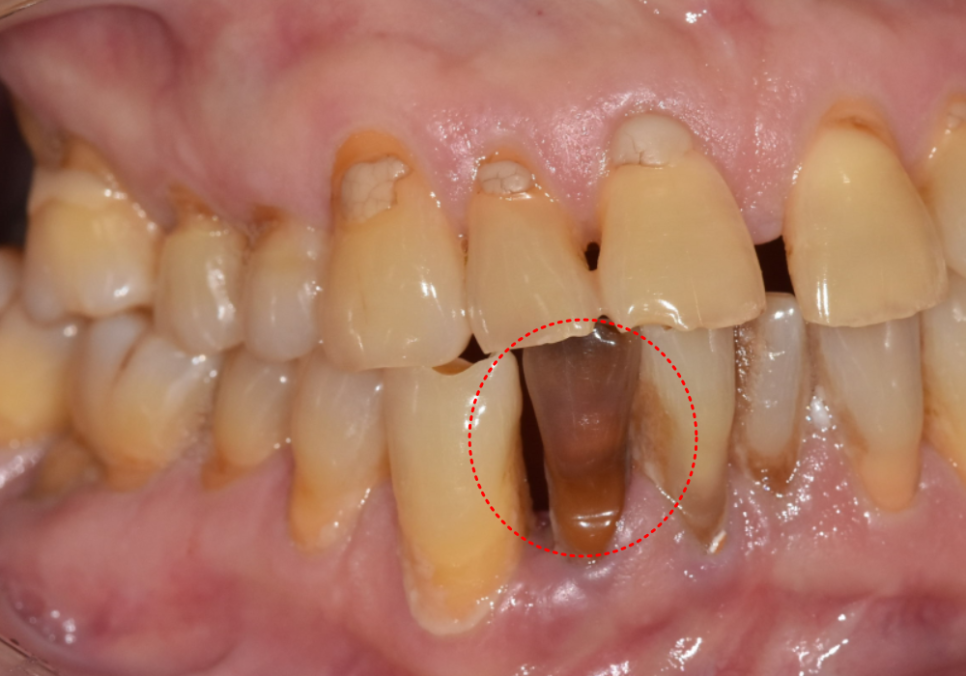

치아에 외상을 입거나 신경이 손상되면

치아가 회색이나 갈색으로 어두워집니다.

이런 경우도 치아 내부에서 시작된 변색이라

일반 미백으로는 효과를 보기 어렵습니다.